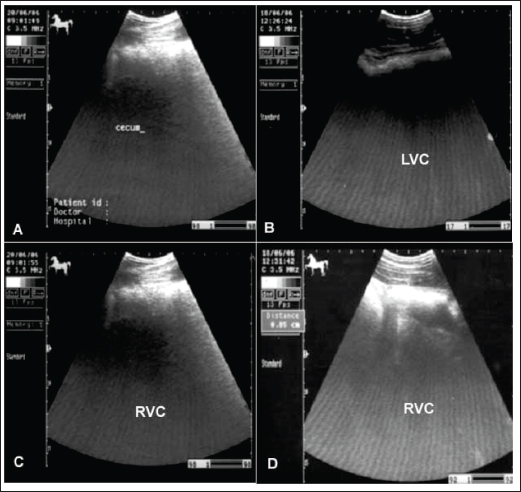

Flatulent colic

Flatulent colic (gastric tympany, wind colic, and tympanic colic) is caused by increases in fermentation or ineffectual gastrointestinal motility or may be secondary to partial luminal obstruction and aerophagia (wind cribbing) (Le Jeune and Whitcomb, 2014). Other causes include interruption in gastrointestinal motility resulting from stress, excitement, pain, or parasympatholytic medication, ileus secondary to uremia, liver disease, vascular compromise (thromboembolic colic), or surgical massive manipulation of the intestines, late pregnancy, impaction, displacements, constipation, and space-occupying masses (Worku et al., 2017). The cause of most cases of intestinal tympany is not well-known, although feeding on a highly fermentable green diet is considered to be a predisposing factor. In addition, the feeding of grains-rich diets is associated with changes in colonic inclusions that might initiate tympany. This condition may occur secondary to obstructive intestinal diseases that prevent the normal passage of gas and ingesta (Worku et al., 2017).

In flatulent colic, temperature and respiration are elevated, the pulse rarely exceeds 70 beats /minute, and the mucous membrane is pale. Rectal examination revealed gas-filled portions of the intestines, and distended portions of the jejunum or ileum could be felt as thin-walled loops without sacculations and taeniae. Auscultation of the abdomen revealed decreased peristalsis but not totally absent. In addition, stomach distension may occur resulting in severe signs of pain, sweating, pawing, and hyperactivity (Worku et al., 2017). Horses with flatulent colic usually appear bloated, especially in the right flank, and show signs of severe pain, which may be intermittent or constant with particularly painful spasms. Auscultate pinging sounds are present over the right dorsal flank and midabdominal area (Beccati et al., 2011). The main diagnostic techniques for the tympanic colic in equines are radiography and sonography. Ultrasonographically, Tharwat et al., (2008) reported that flatulent colic bowel appeared distended with gas that prevented visualization of the ingesta inside, and the sacculations disappeared. The peristaltic activity of the gas-distended segment is decreased or absent (Tharwat et al., 2008).

The cecum of horses with flatulent colic appears thin-walled due to gas distension; absence of sacculations; hypomotility on real-time ultrasonography, and the gases in the cecum prevent visualization of the ingesta inside the cecum (Le Jeune and Whitcomb, 2014). In comparison to healthy horses, the cecum is identified by its sacculations and contractions. The left ventral colon appears with a thin echogenic wall, the absence of sacculations, and the gases inside hinder the visualization of the ingesta. The right ventral colon compared to clinically normal horses shows the absence of sacculations and might be with thin or increased wall thickness, and this agrees well with Scharner et al., (2002), while in control horses it is characterized by the presence of sacculations, bright hyperechoic line, and the inability to identify the entire circumference of its wall (Fig. 5). Horses suffering from severe gas accumulation may collapse where postmortem examination confirms the diagnosis (Tharwat et al., 2008).

Fig. 5. Ultrasonogram of the cecum, left ventral colon (LVC), and right ventral colon (RVC) in 4 horses with flatulent colic. In A, the cecal wall appears echogenic in the absence of sacculations. In B, the LVC shows an echogenic wall with no sacculations. In C, the RVC shows a thin wall that appears echogenic in the absence of sacculations. In D, RVC appears in the absence of sacculations and with increased wall thickness. These organs contain a large amount of gas, which hinders their visualization.